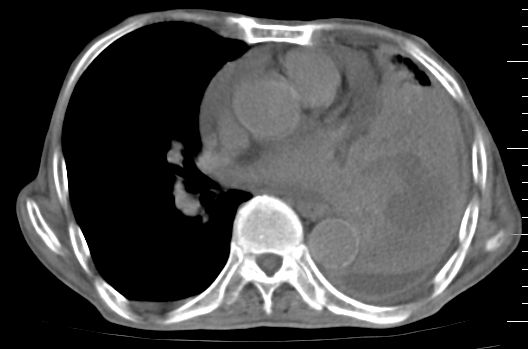

标题: CT10141:男、84岁,咳嗽、咯血1年。 [打印本页]

标题: CT10141:男、84岁,咳嗽、咯血1年。

支持左侧中央型肺癌伴下叶肺不张\\纵隔淋巴结转移.左侧包裹性胸腔积液\\心包积液.左侧少量胸腔积液..慢性支气管炎伴部分间质纤维化.

支持:左侧中央型肺癌伴下叶肺不张\\纵隔淋巴结转移.左侧包裹性胸腔积液\\心包积液.左侧少量胸腔积液..慢性支气管炎伴部分间质纤维化.另:支气管分支根部明显阻塞 狭窄,内膜凸凹不平,提示内膜增生物。

咯血病史较长,左肺下叶实变,体积未明显缩小,隐约可见血管影及坏死阴影,双肺门及纵隔淋巴结增大,心包增厚积液,纵隔右移位,单侧胸腔积液,首先考虑:大叶型肺泡癌伴纵隔心包转移。